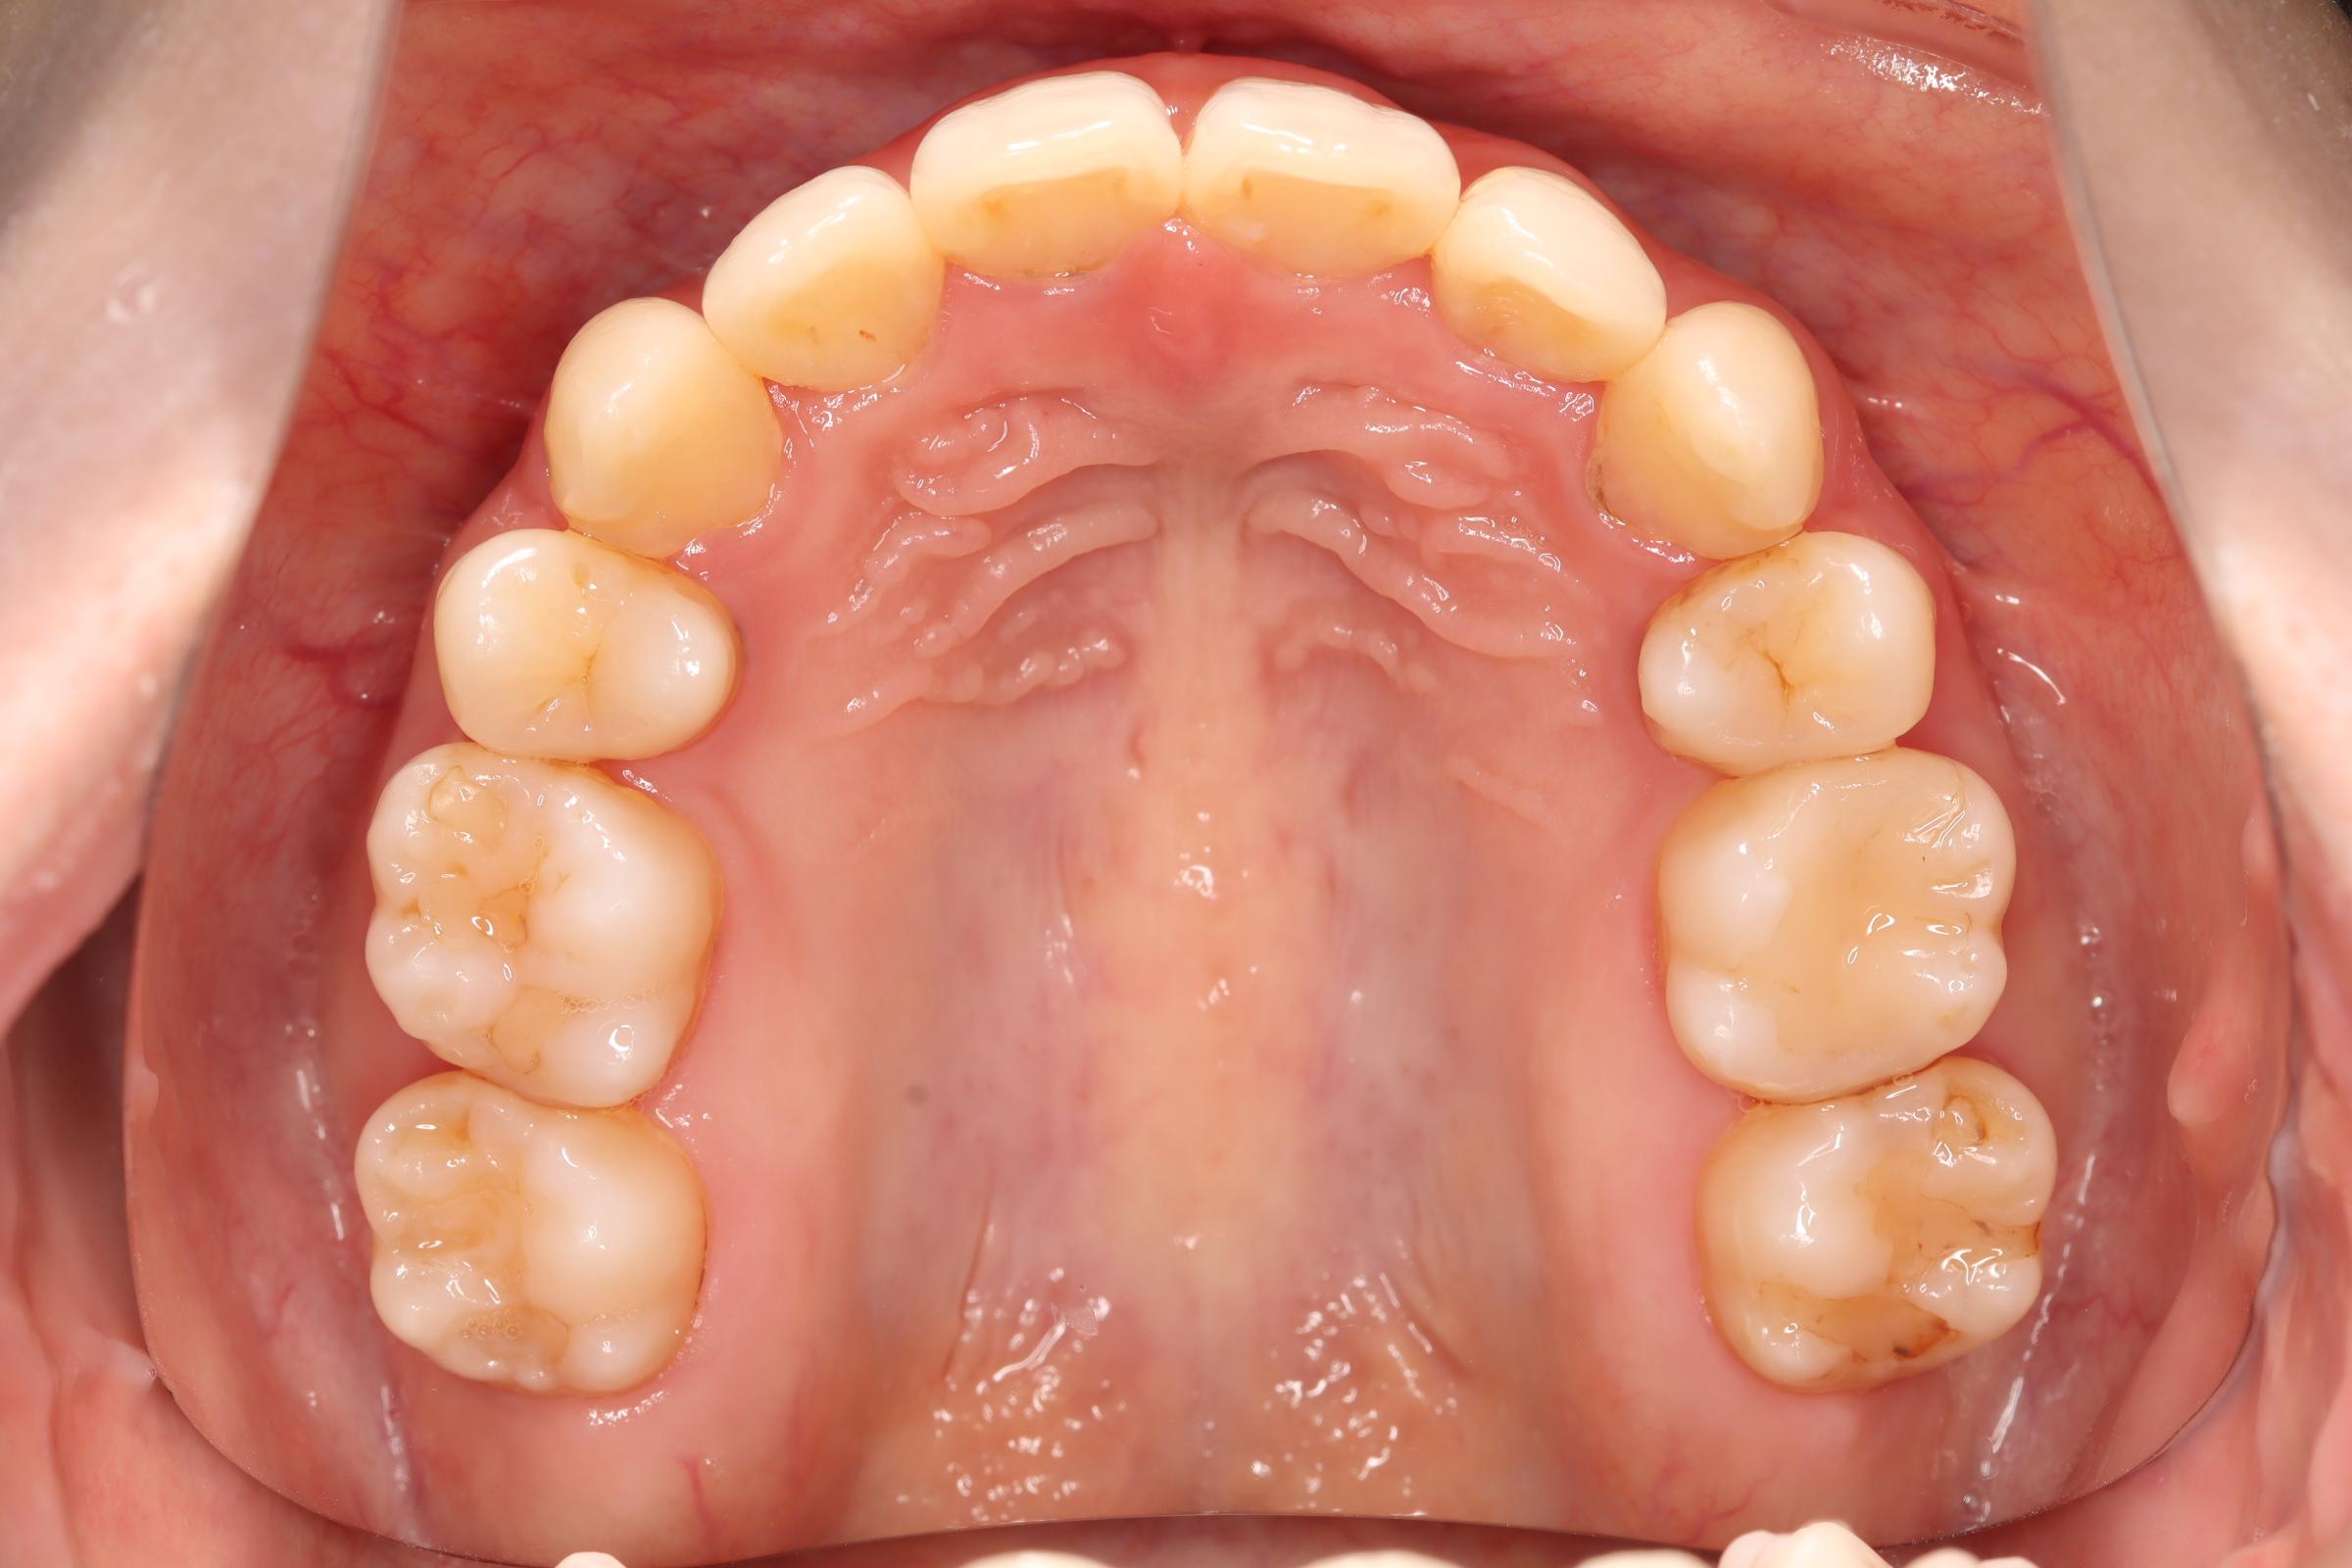

舌側(リンガル)矯正での叢生(ガチャ歯)の治療

| 治療後 | 前歯から奥歯まで全体的に緊密な咬み合わせになっています。 歯のガタつきが無くなることにより、綺麗な見た目と歯磨きのしやすい口腔内環境になりました。 また突出感のあった口元もすっきりして綺麗なEラインとなり横顔も変化しました。 しっかりとしたかみ合わせを作ることにより、綺麗な歯並びになります。 |